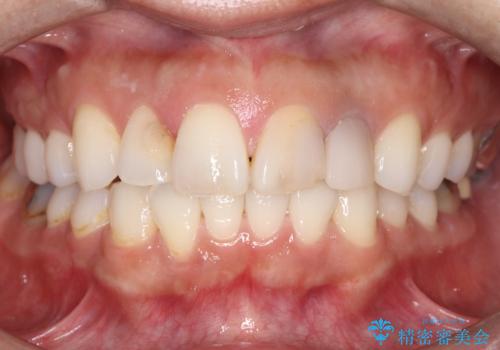

前歯の突出を防ぎながらガタつきを解消。上下左右4番抜歯による審美ワイヤー矯正

前歯の突出と下顎の偏位を改善。審美ワイヤーで整えるバランスの良い歯並び